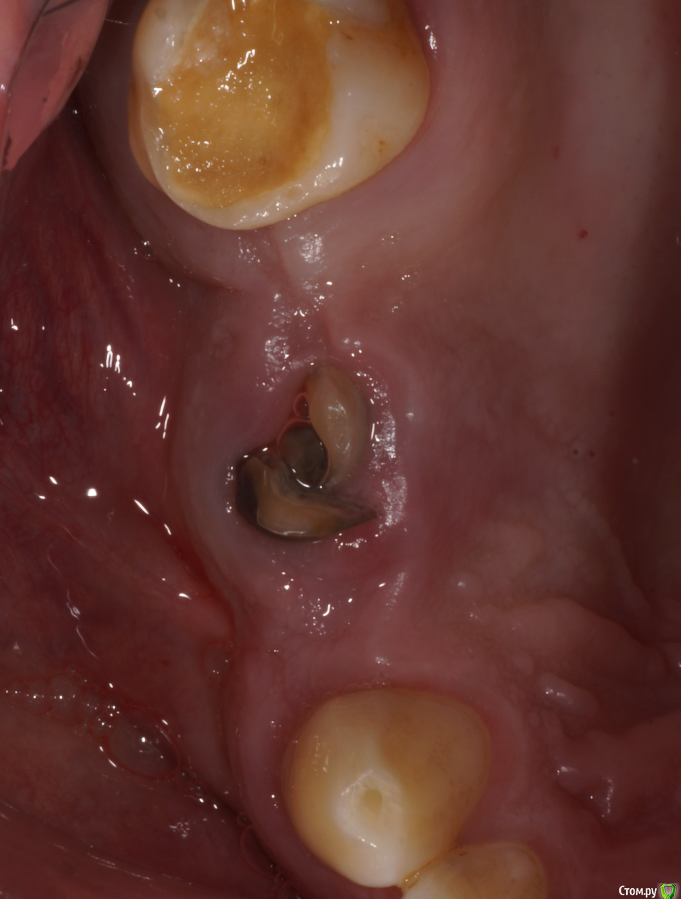

Ах да, забыл совсем. Удалил по ходу действия 1.8, обратите внимание на пазуху по КТ - септа в проекции 1.7 так удачно отделила отекшую слизистую от области синуса)

Это я косанул. Хотел ровнехонько в 1.4 а вышло немного дистальнее. Ортопед, правда, уже одобрил, я немного волновался в первые дни.